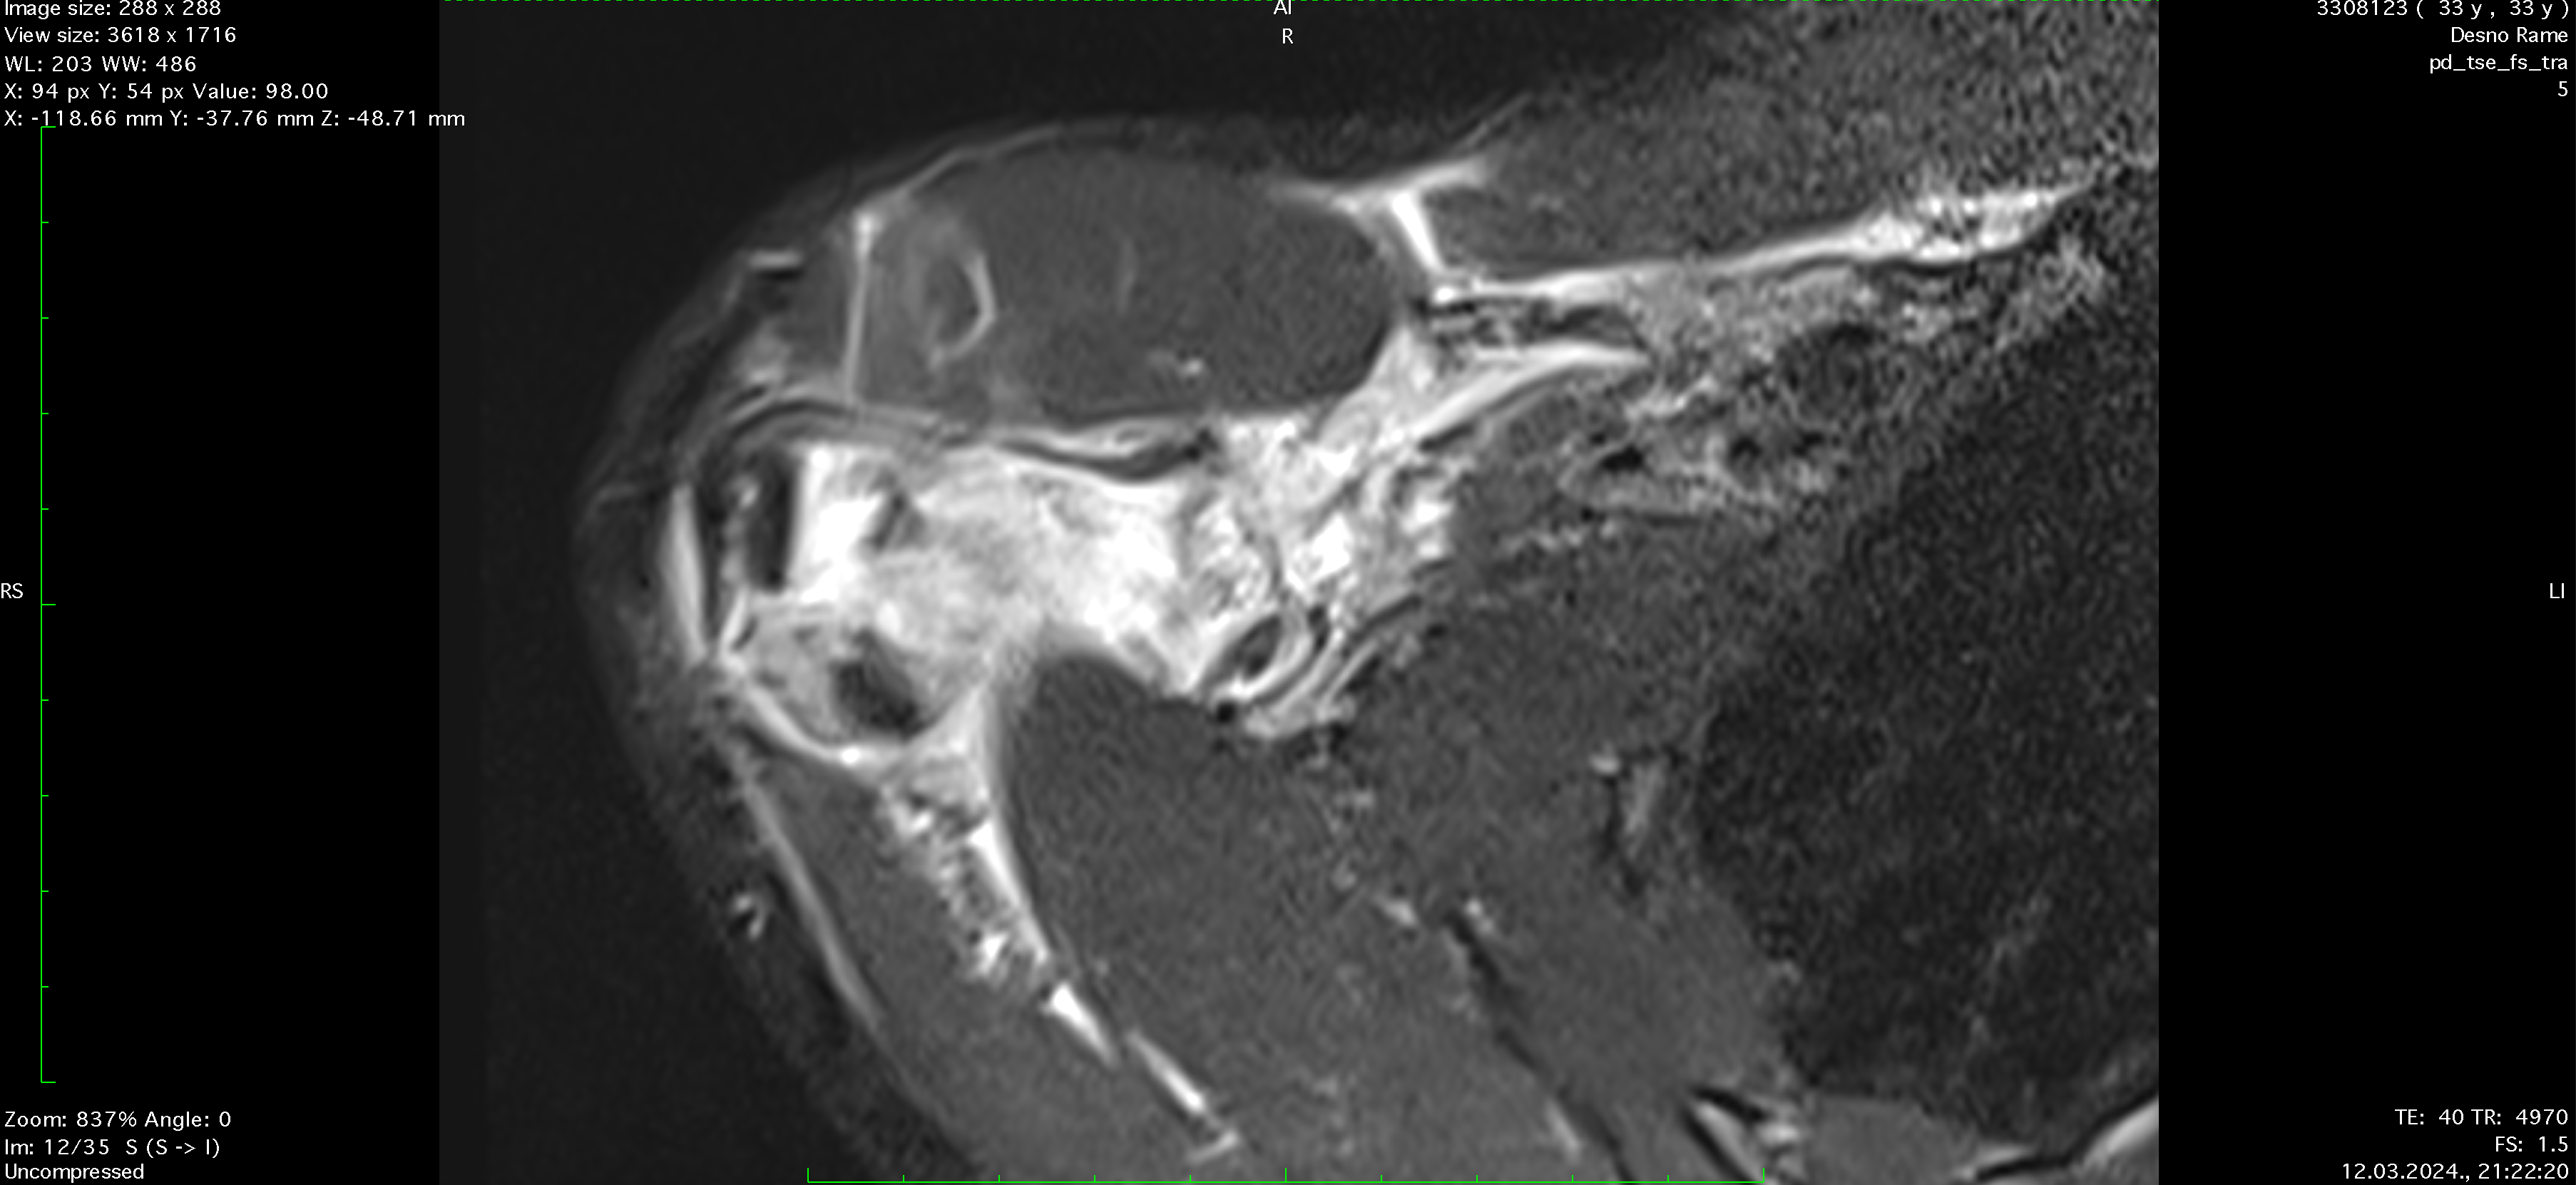

Ten days after the injury, the player's pain level had decreased to 3 out of 10, and nearly full ROM had been regained. A follow-up MRI showed significant recovery, with the AC joint fully reconnected and healed ligaments, though there was some residual edema caused by inflammation from the prolotherapy. Treatment continued for another week, during which the player engaged in more active exercises, including mobility, weight-bearing, and rotator cuff strengthening. While fast movements initially caused stiffness, this resolved within 3 to 4 days.

Reconnection of coracoclavicular ligament, soft tissue, trapezius m., regeneration, formation of AC joint capsule visible after only 8 days of therapy.